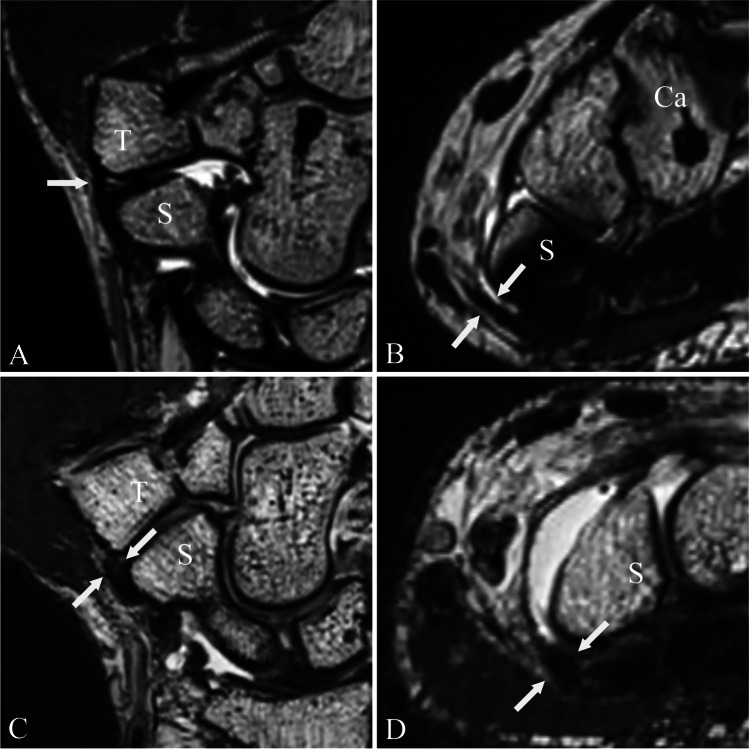

Fig. 4.

Radiopalmar scapho-trapezial ligament. Proton density-weighted (SPACE) images of a MR wrist arthrogram in coronal double oblique (a and c) (as shown in Fig. 3a) and axial plane (b and d). Images a and b show a normally appearing radiopalmar scapho-trapezial ligament (rpSTL) (white arrows) of a 31-year-old male asymptomatic patient. The rpSTL originates from the distal pol of the scaphoid and inserts into the ridge of the trapezoid. Note the normal low signal intensity of the ligament and the distinct morphology. Images c and d show the rpSTL (white arrows) of a 44-year-old male symptomatic patient with pain over the STT joint. Note the increased signal intensity and the indistinct ligament morphology of the rpSTL. Abbreviations: S, scaphoid; T, trapezium